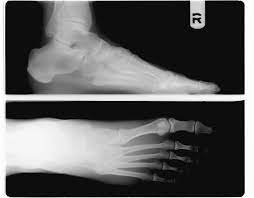

구조적으로 발바닥의 아치가 정상보다 낮아 흔히 평발로 불리는 편평족이나, 아치가 정상보다 높은 요족(cavus) 변형이 있는 경우 족저근막염의 발생 가능성이 높다. 또한 다리 길이의 차이, 발의 과도한 회내(발뒤꿈치의 바깥쪽 회전과 발목의 안쪽 회전의 복합 운동) 변형, 하퇴부 근육의 구축 또는 약화 등이 있는 경우에도 족저근막염을 유발할 수 있다. 족저근막의 발뒤꿈치뼈 부착 부위에 뼛조각이 튀어나온 사람들 중 일부에서 족저근막염이 발생하기도 한다.